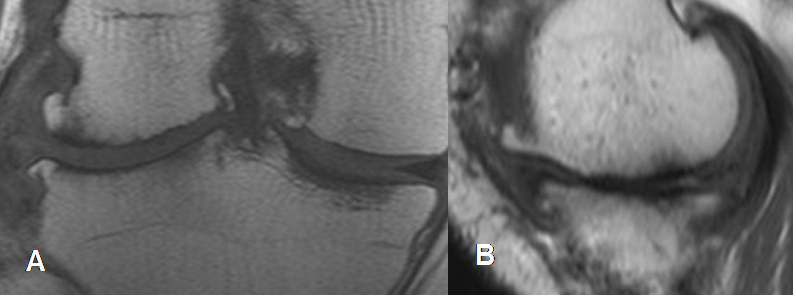

Fig 84. Falsa ruptura meniscal.

A y B: RM sagital en T1. En A hay imagen en sentido oblicuo en el cuerno anterior, que se comunica con la superficie articular superior, sugestiva de ruptura meniscal. En el corte sucesivo B, se aprecia que la imagen está compuesta por el cuerno anterior del menisco (Flecha delgada) y el ligamento transverso (Flecha gruesa) y no corresponde a ruptura.

Fig 85. Falsa ruptura meniscal.

A y B: RM sagital en T1. Imagen en sentido vertical, sobre el cuerno posterior del menisco externo en A, que se comunica con la superficie articular superior, compatible con ruptura meniscal. En el siguiente corte B, esta imagen está formada por el borde del menisco y el tendón poplíteo, correspondiendo a falsa ruptura.